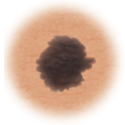

Moles (nevi)

Small skin marks caused by pigment-producing cells in the skin. Moles can be flat or raised, smooth or rough, and some contain hair. Most moles are dark brown or black, but some are skin-colored or yellowish. Moles can change over time and often respond to hormonal changes.

Most moles are benign and no treatment is needed. Some benign moles may develop into skin cancer (melanoma). See below for signs.

Atypical moles (dysplastic nevi)

Larger than normal moles (more than a half inch across), atypical moles are not always round. Atypical moles can be tan to dark brown, on a pink background. These types of moles may occur anywhere on the body.

Treatment may include removal of any atypical mole that changes in color, shape, or diameter. In addition, people with atypical moles should avoid sun exposure, since sunlight may accelerate changes in atypical moles. People with atypical moles should see a healthcare provider for any changes that may indicate skin cancer.

Certain moles are at higher risk of changing into malignant melanoma, a form of skin cancer. Large moles that are present at birth and atypical moles have a greater chance of becoming cancerous. Finding cancerous skin growths early is important because that’s when treatment is most likely to be effective. Removing the melanoma through surgery seems to work best as the treatment. When a melanoma is diagnosed early, surgery usually removes all the cancer.

Use this ABCDE chart below to help you see changes in your moles at the earliest stages. The warning signs include: